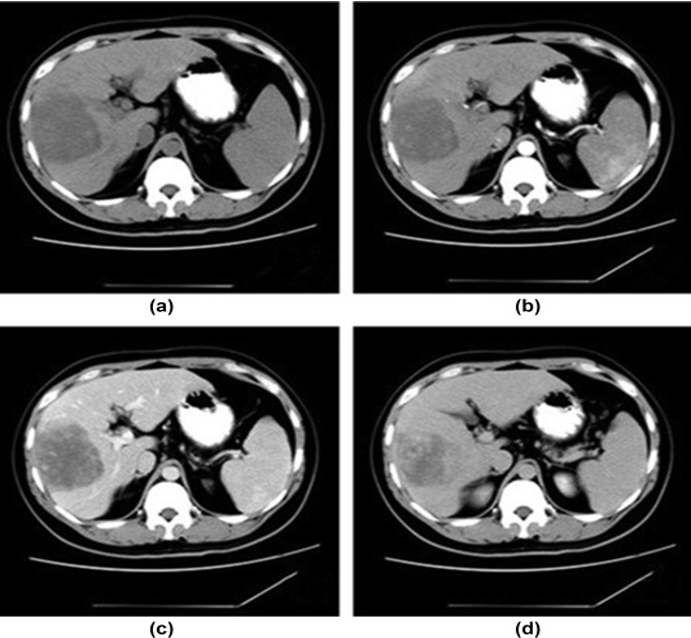

Summary of T1, and the various phases of the contrast study illustrating the nature of the focal liver lesion.

Note the enhancement of the central scar only on the delayed images when the rest of the lesion has washed out.

On the arterial phase, the lesion demonstrates intense homogenous enhancement, except for the central scar.

(a) unenhanced, (b) Arterial, (c) portal, and (d) delayed phases. After intravenous contrast administration, the nodule shows stable peripheral rim-like enhancement (arrow).